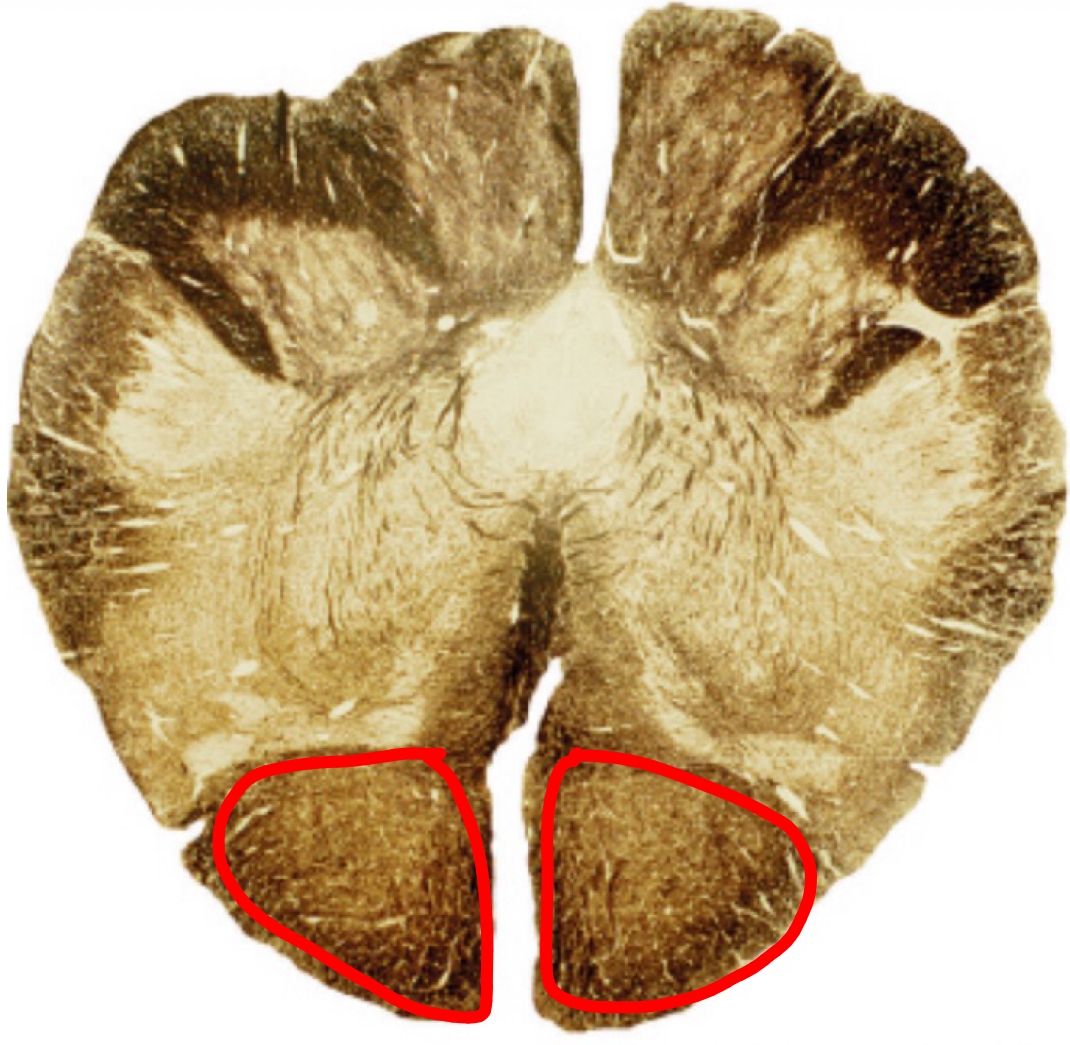

pontine nuclei caudal pons

corticospinal fibers caudal pons

middle cerebellar peduncle caudal pons